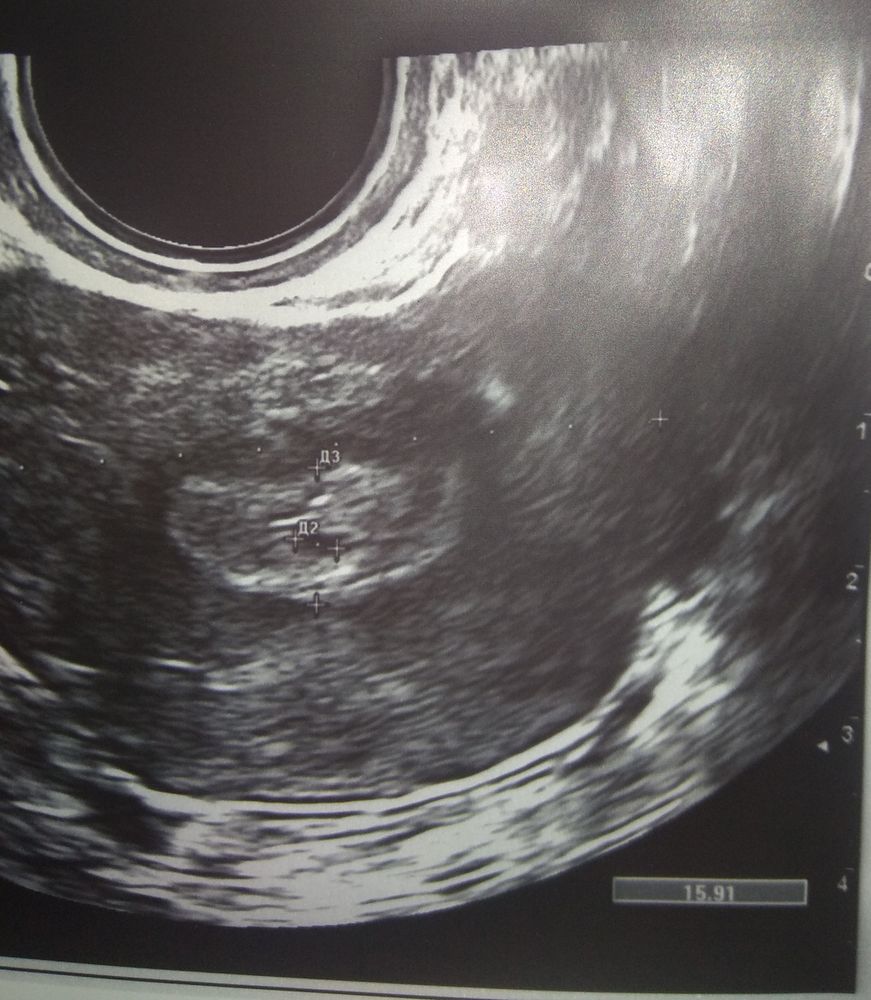

сегодня на УЗИ увидели плодное яйцо 3 мм😭😭😭 в заключении написано, что беременность малого срока 2-3 недели

Фото пя 3мм.